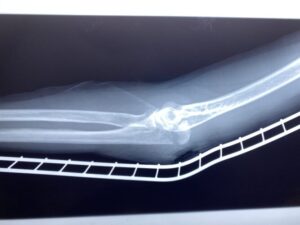

第28回整骨研究会「賜恩」研究会を開催し、上腕骨顆上骨折伸展型の研修をし…

春日部市市民活動センター(上腕骨顆上骨折)

第28回整骨研究会「賜恩」研修会開催